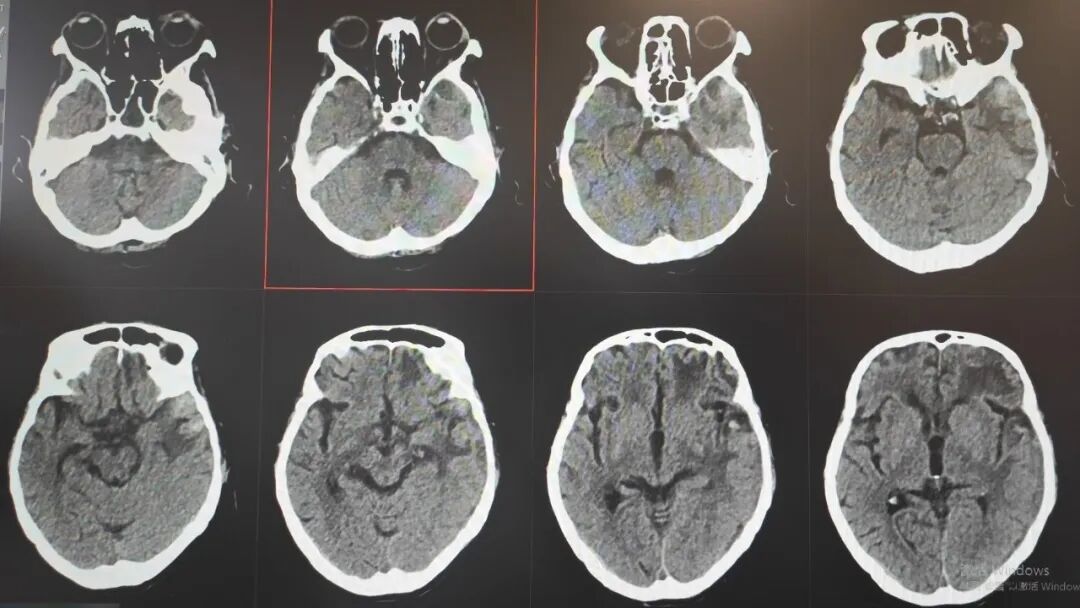

那段日子,病情几度反复、险象环生,医护人员寸步不离守在床前,24小时紧盯生命体征,精细调整每一步治疗方案,昼夜不敢有丝毫松懈。在一次次与死神的拉锯中,他们凭着耐心与坚守,终于等来了转机:阿婆从深度昏迷慢慢睁开双眼,从卧床不起到能在搀扶下缓缓起身,每一个微小的进步,都藏着无数个日夜的坚守与温暖,让绝境之中绽放出生命的微光。

出院时

如今,吴阿婆已顺利闯过最凶险的危险期,身体恢复良好,已经康复出院。家属看着老人从命悬一线到平安好转,激动又难以置信,反复向医护人员表达着最真挚的谢意,这份跨越绝境的重生,是医患同心最温暖的见证!